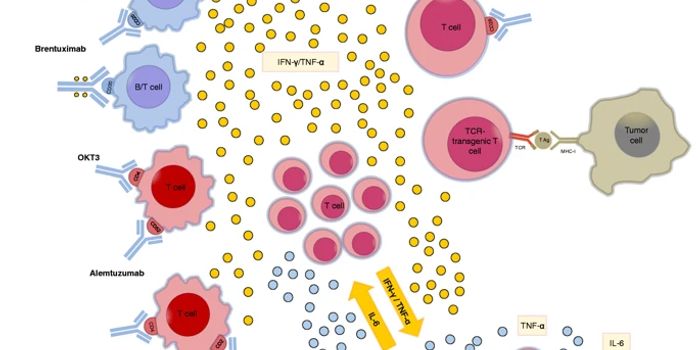

JUN 04, 2024Drug Discovery & DevelopmentModerate-vigorous intensity exercise could improve the efficacy of antibody therapies when treating leukemia. The corres ...